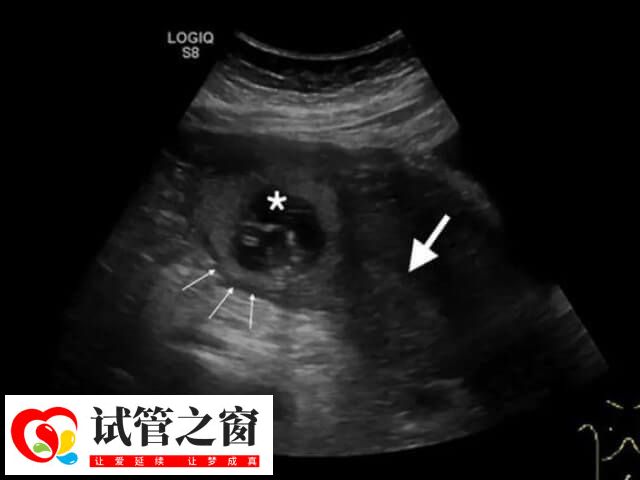

一般來說,試管移植后胚胎的最佳著床位置,是在子宮底部正中。因為這個位置的內膜厚度適中,血供和營養豐富,有利于胚胎的生長發育,但由于每個女性的宮腔內環境不同,胚胎移植后的著床位置也不同,有胚胎移植后會在子宮體前壁、后壁、側壁這些位置著床,這都是因人而異的。所以移植后的胚胎并不會一直都待在這個地方而是會在女性的宮腔內游走3-5天,尋找合適的位置著床。

醫生將胚胎移植到女性患者宮腔后,胚胎會在宮腔中處于游走狀態,在經過幾天時候后才會進行著床。而著床的位置是根據每個患者的不同宮腔環境有所差異,至于胚胎著床過程是怎樣,如下所示:

2、在移植后的3-7天,它會長出1個小尾巴,在子宮腔內找到一個舒服的位置,如子宮體前壁、后壁、側壁這些位置,鉆進子宮壁內,從而完成著床;